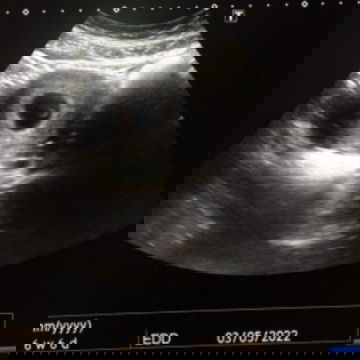

Scan 6w nampak jantung baby tknampak

Salam ad tk mcm sy bila scan 6w nampak ketulan kecil je doc bgtau jantung sbb2 kelip2... Tp baby xnampak lg... #ingintahu #firstbaby